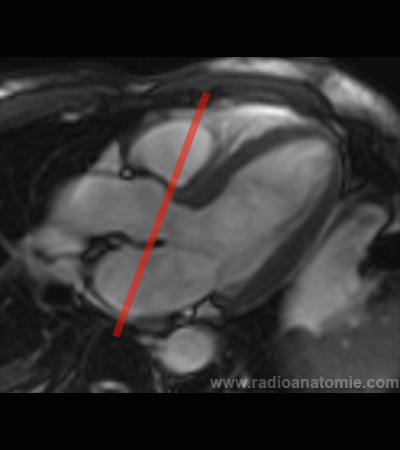

Plan petit axe